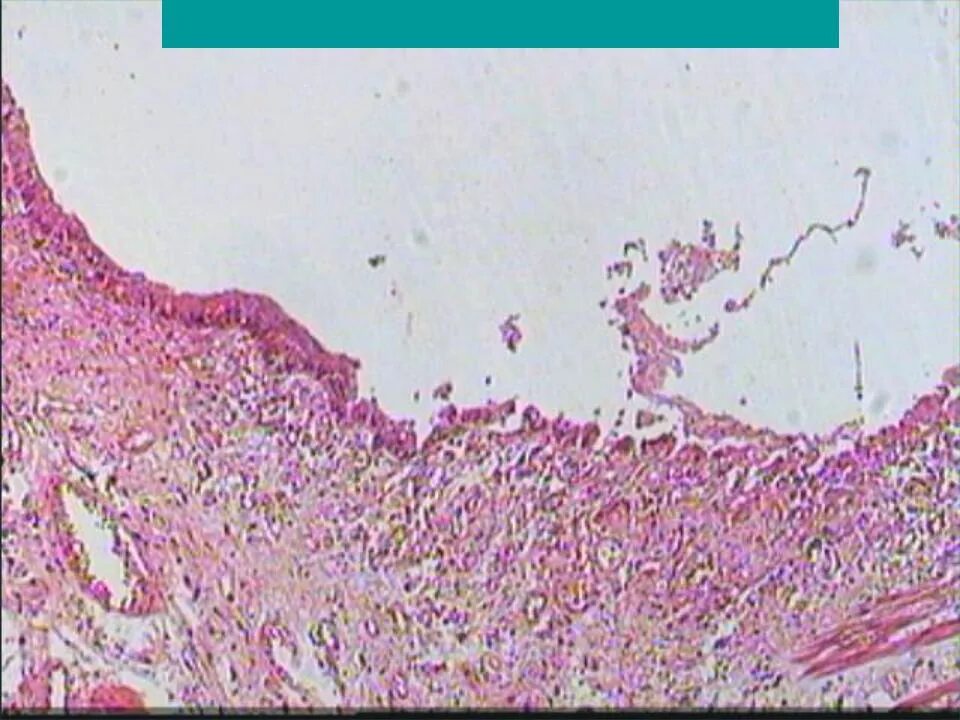

Язва гистология